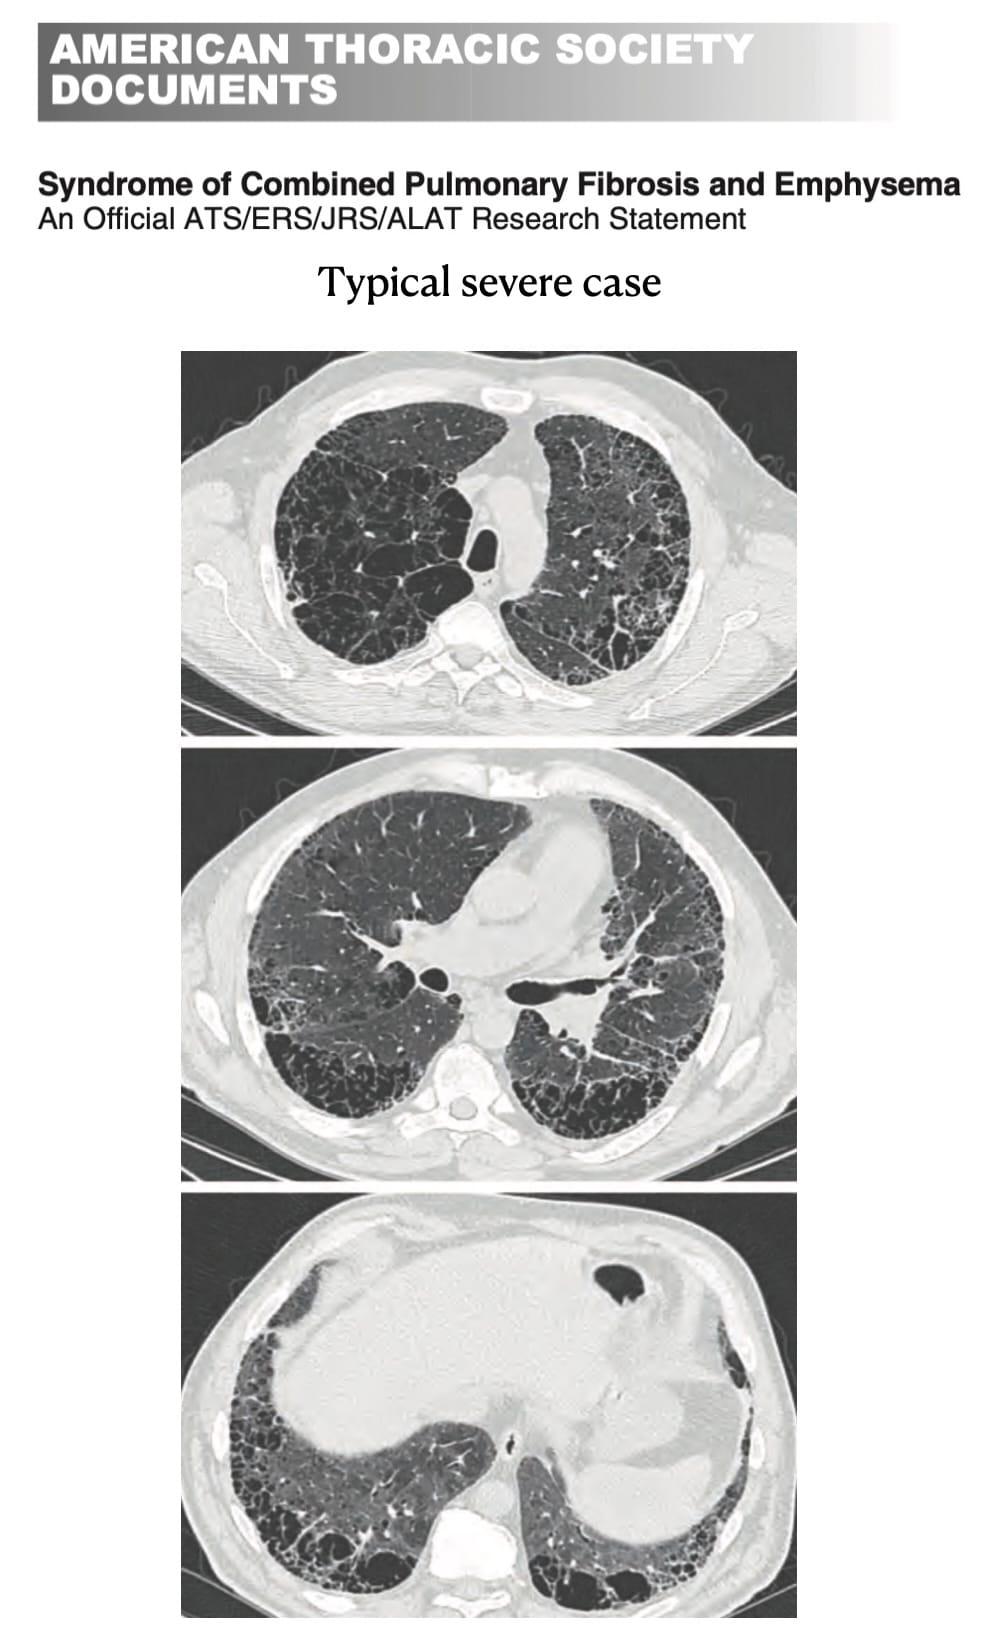

- New concepts in Interstitial Fibrosis